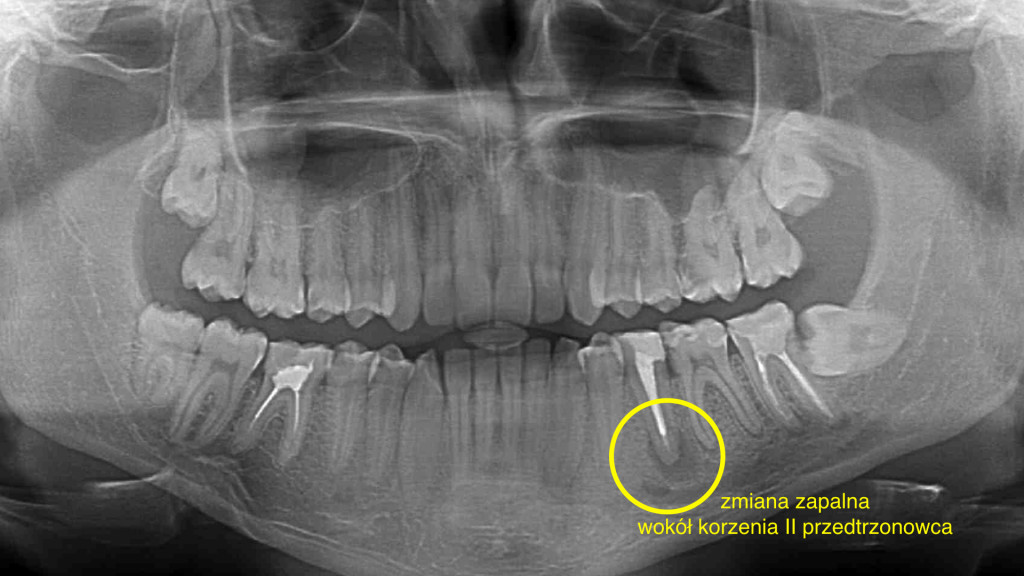

Drugi przedtrzonowiec w żuchwie uratowany. W wyniku terapii endodontycznej nastąpił całkowity zanik zmiany zapalnej w rejonie drugiego przedtrzonowca w żuchwie po lewej stronie. Leczenie kanałowe z użyciem mikroskopu była dodatkowo utrudniona ze względu na pacjenta i jego odruch refluksu. Pacjent zgłosił się do placówki NZOZ Stomatologia Bez Bólu bardzo narzekając na ból, jak określił nie do wytrzymania w żuchwie po lewej stronie. Podczas badania radiologicznego OPG i RVG stwierdzono dużą zmianę zapalną w okolicach wierzchołka korzenia drugiego przedtrzonowca w żuchwie po lewej stronie, generującą zanik kość w tym sektorze żuchwy.

Po 10 miesiącach na zdjęciu kontrolnym widać wyraźnie całkowite odbudowanie struktury kostnej okalającej korzeń zęba – drugiego przedtrzonowca w żuchwie po lewej stronie.